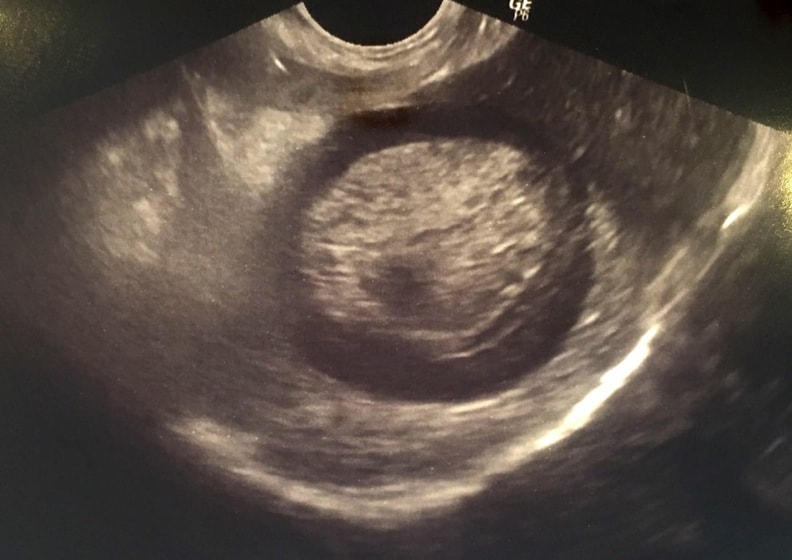

胆嚢の超音波検査所見

超音波検査所見

胆嚢粘液嚢腫エコー